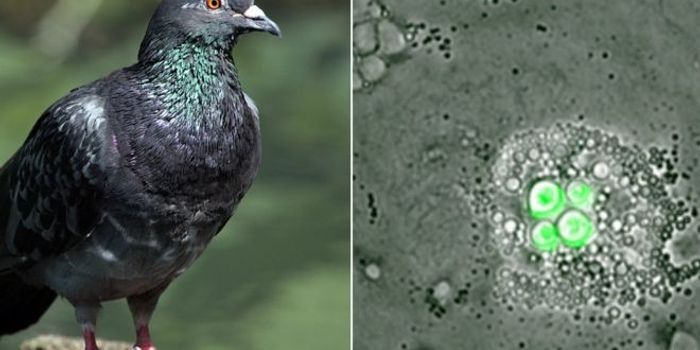

FEB 21, 2016Plants & AnimalsBirds’ immune systems reportedly have a great defense against a fungal infection from Cryptococcus neoformans that ...